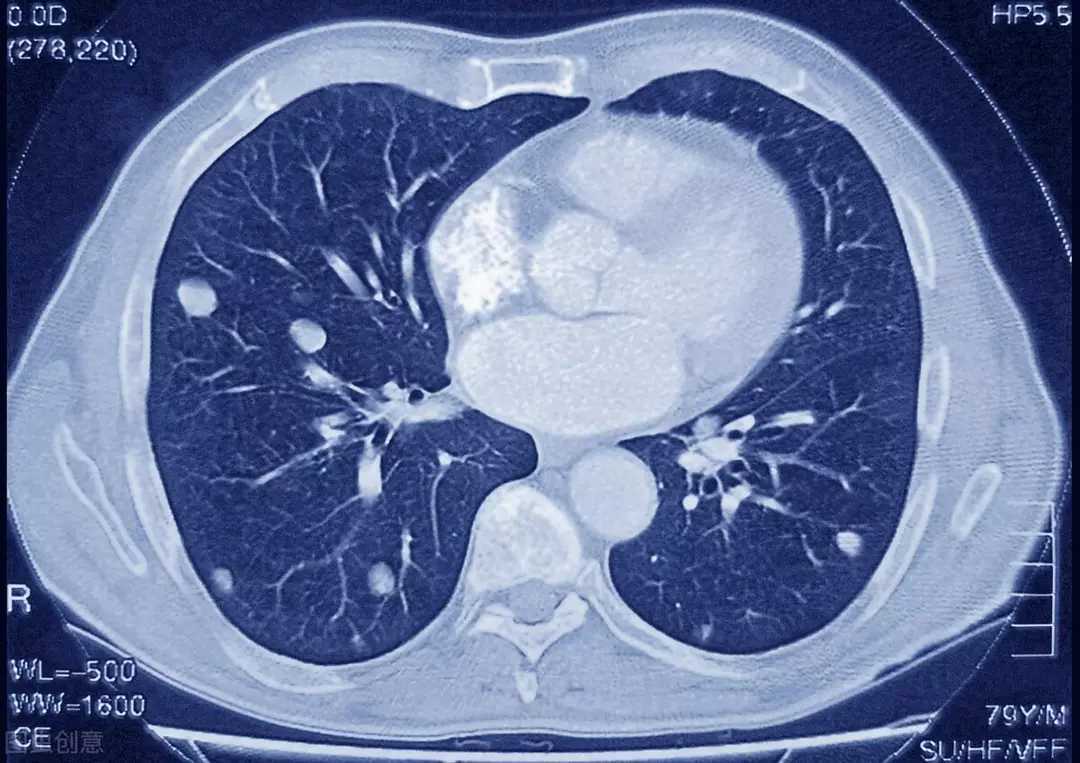

它在胸部CT上主要表现为:双肺多发的粟粒样小结节影,直径一般在2—4mm左右,典型的患者一般还有“三均匀”的特点,也就是大小均匀、分布均匀、密度均匀。

急性粟粒型肺结核结节的“三均匀”特点,也就是大小均匀、分布均匀、密度均匀。

同时,由于它属于血行播散,所以可能还会合并肺门及纵隔淋巴结、脊柱、肾上腺以及肾脏结核等,可以累计全身多个组织器官。